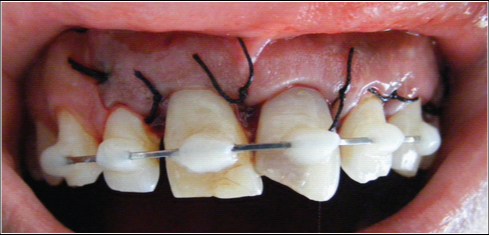

The root surfaces were treated with tetracycline solution for 30 seconds and then replanted in the alveolar socket in its original position [Table/Fig-11]. Semi-rigid splinting was done using a 21-gauge stainless steel orthodontic wire for 10 days [Table/Fig-12] and a postoperative IOPA radiograph was taken [Table/Fig-13]. The complete procedure took 20 minutes of extraoral time.

Postoperative intraoral view after splinting,